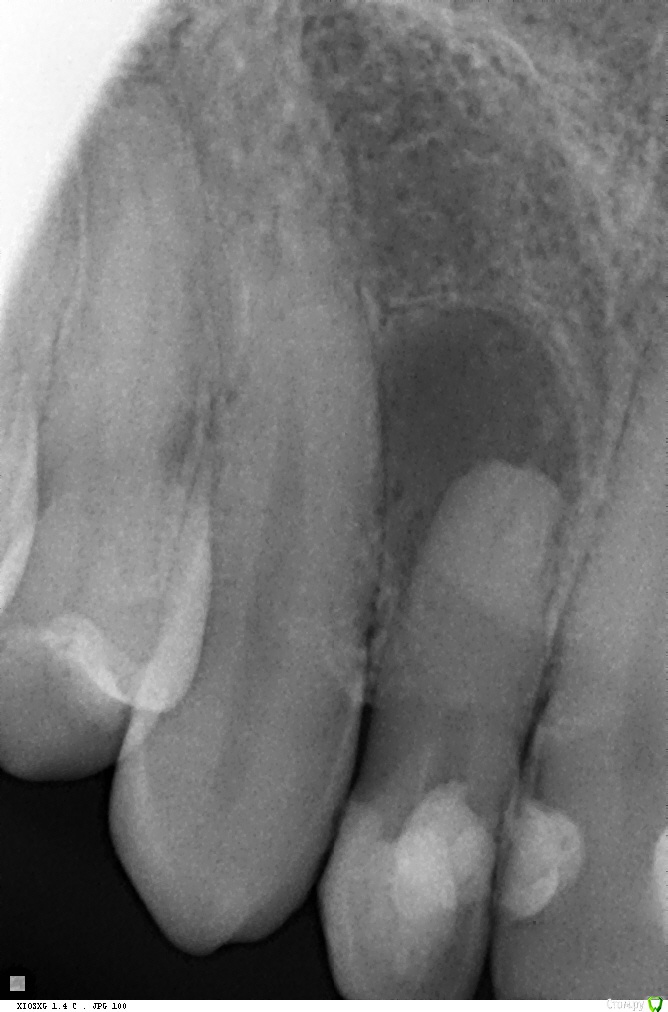

Киста 12 зуба, склерозированный канал, резорбция корня

Зуб лечила ранее, меняла пломбы по мере необходимости. Думала, что он давно депульпирован, тк никогда не беспокоил, но по какой причине получилось так....не знаю. При случайном обследовании у ЛОРа на КТ была обнаружена киста 12 зуба. Процесс явно очень старый и запущенный.

Канал зуба пытались пройти 3 раза под микроскопом. Каждый раз понемногу продвигаются))) Предложили вариант апикальной хирургии, НО....При апикальной хирургии ортодонты от меня открещиваются-зуб вылетит. Да и у апикального еще не была- может и не возьмется(

В общем задача- пройти канал!